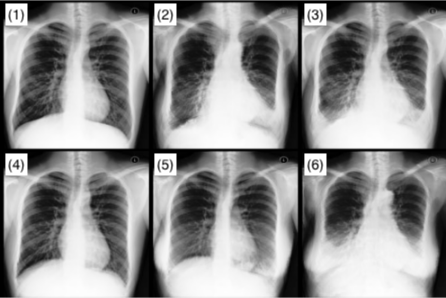

Refer to caption

Figure 4: (a) CF Regularisation on MIMIC-CXR. (b) MIMIC-CXR CFs from model trained on 40% labels. From top-left: (1) original: white, healthy, 20-year-old male, (2) do(age=90age90\text{age}\!=\!90), (3) do(diseased), (4) do(asian), (5) do(female), (6) do(all).

From the cells on the diagonal of Table 4.1.2 (right), we see that our method tends to improve upon the supervised approach with regards to implementing interventions. The other cells are essentially a measure of reconstruction quality, since they involve evaluating variables that have not been intervened on. As such, the closeness of these values for the various models suggests that the achieved counterfactual generation gains are primarily due to differences in the causal inference component. This indicates that it would be fruitful to focus future efforts on improving this section of the model. This holds for both SSL and Flexible, demonstrating that practitioners implementing our approach need not prioritise achieving full labelling for any given sample over collecting as many labels as possible, bolstering the usability of the model. Fig. 4a demonstrates the increased interventional accuracy provided by counterfactual regularisation. Moreover, as shown in Figure 4b, our model is able to exhibit clear visual changes for the various counterfactuals, indicating the numerical results are not due to minute changes undetectable to the human eye [2]. To build upon this, one avenue of future research would be to use this approach to generate additional training data for underrepresented populations in medical datasets and evaluate how this aids downstream tasks.